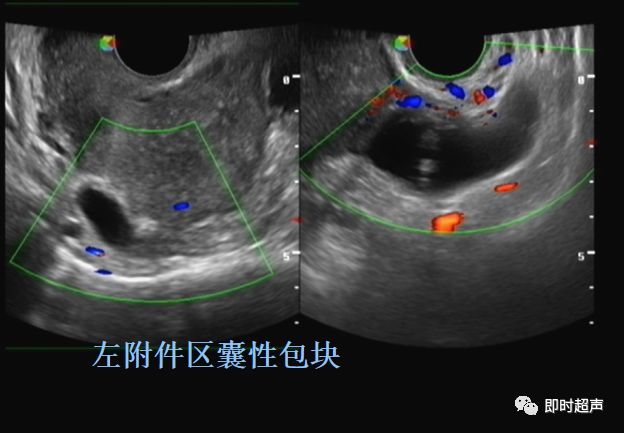

一侧或两侧输卵管行走区卵巢旁探及长管状或腊肠型的囊性包块,囊壁